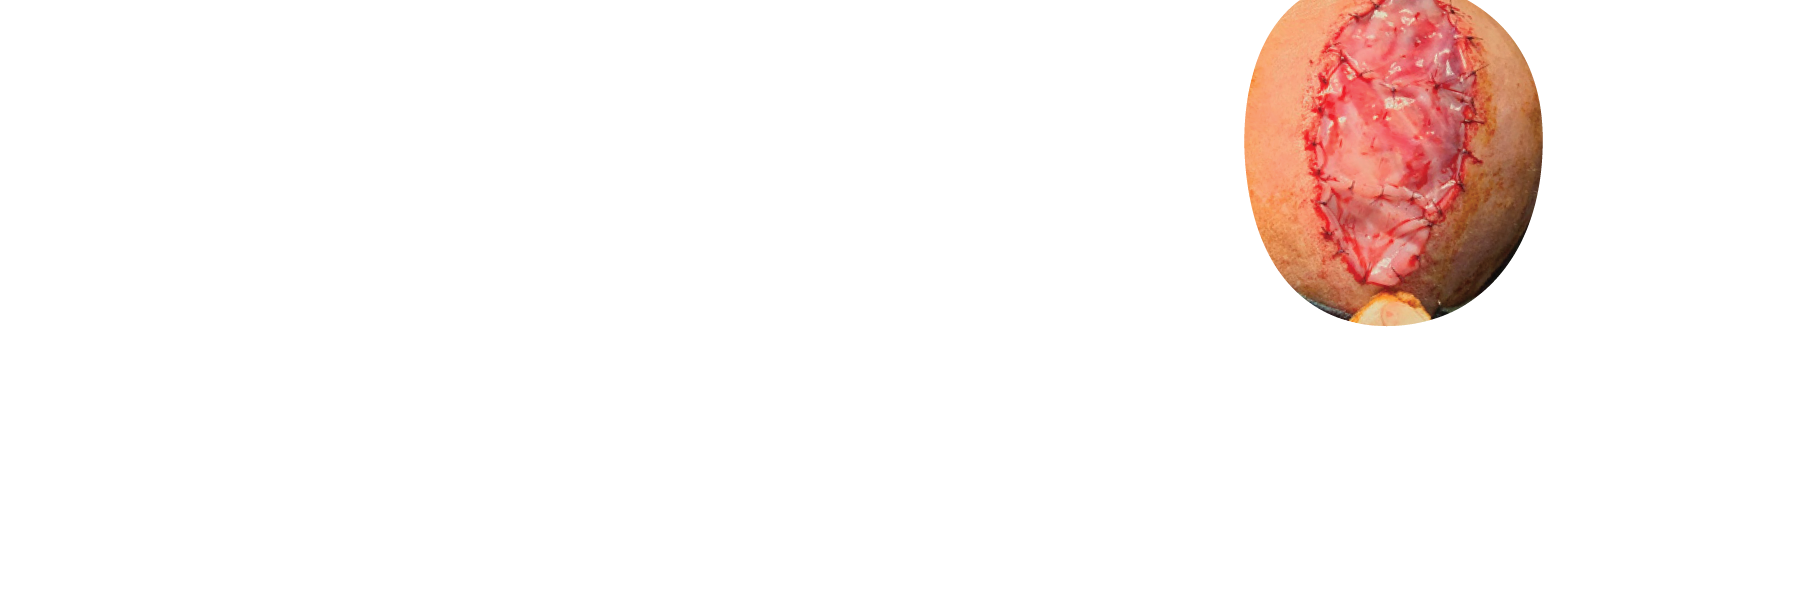

OASIS®

Matrix products

OASIS Matrix products are designed to meet your patients where they are. That means across wound types, severity, and care settings. They are ideal for supporting closure in a variety of wounds and can be used alongside standard care protocols.5,6